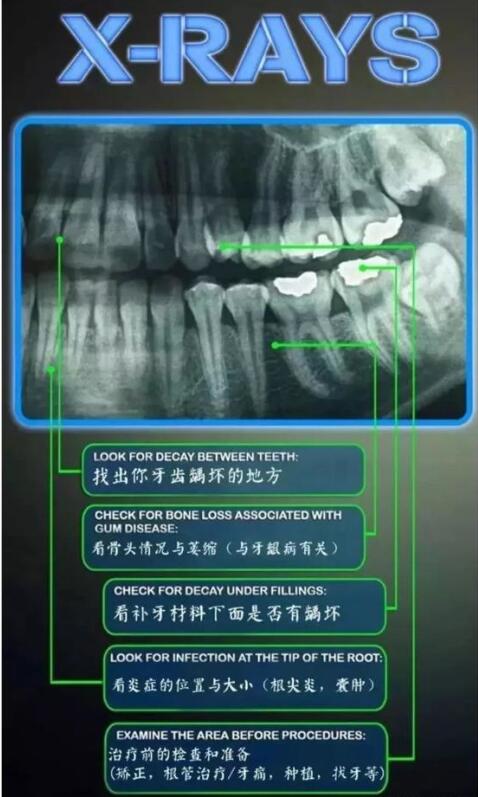

是否有蛀牙,如果有蛀牙,也是需要先治疗的,但是严重的蛀牙补牙需要做根管治疗,费用都是不一定的。

牙周条件好不好,是否有牙周炎,如果有需要先治疗,价格根据牙周炎的严重程度有差异。主要是牙齿畸形程度,越是严重,需要费用越多。还有术前口腔基本情况越复杂,需要处理的牙齿问题就越多,所以价格也会有所增加。

是否需要拔牙,如果是牙齿严重拥挤以及牙齿严重前突等情况,是需要拔牙后矫治的,而且如果智齿需要在之前拔除的话,拔牙需要的费用就更多了。